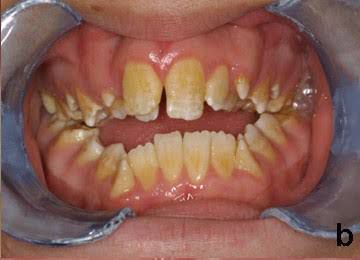

Amelogenesis imperfecta is a disorder of tooth development. This condition causes teeth to be unusually small , discolored, pitted or grooved, and prone to rapid wear and breakage. Other dental abnormalities are also possible. Amelogenesis imperfecta is caused by mutations in the AMELX, ENAM, and MMP20 genes . These genes provide instructions for making proteins that are essential for normal tooth development.